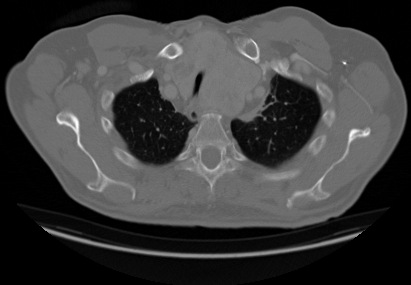

Upload your own CT slice, or click any patient below to instantly see the model classify a real scan.

Try a real scan— click any patient to run inference instantly

INPUT

OUTPUT